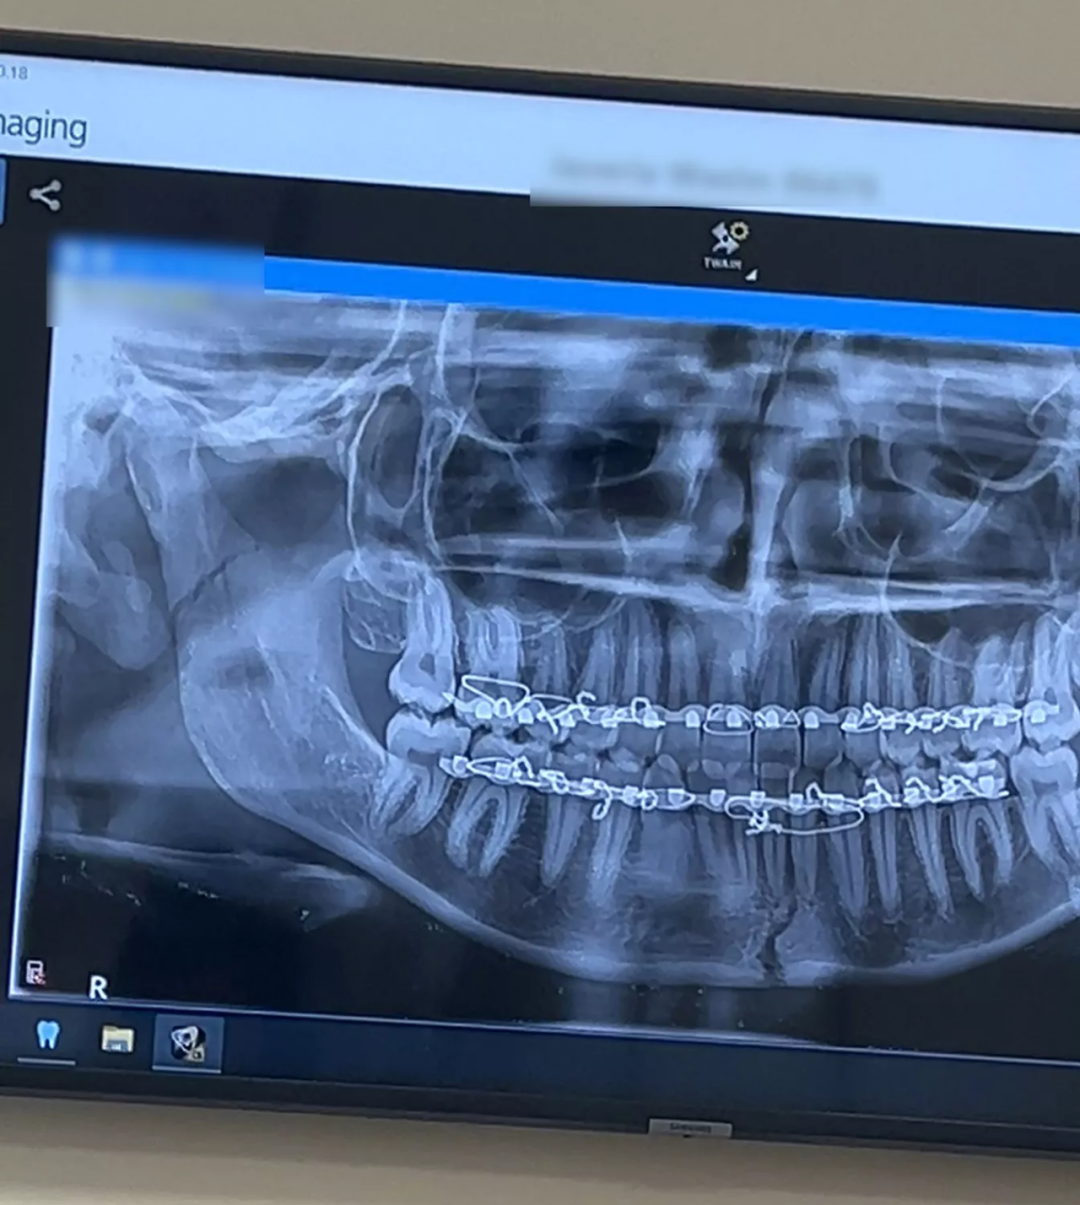

到了医院,通过CT扫描和X光检查,医生发现瓦西姆因咬糖果而导致下巴两处骨折。

“他们告诉我,我的下巴断了,需要用钢丝固定。我当时很震惊;我以为最大的问题是我的断牙。”

之后,瓦西姆不得不接受长达1小时的手术来修复损伤。康复期间,她的下巴还被钢丝固定了整整六周,期间只能吃流食。